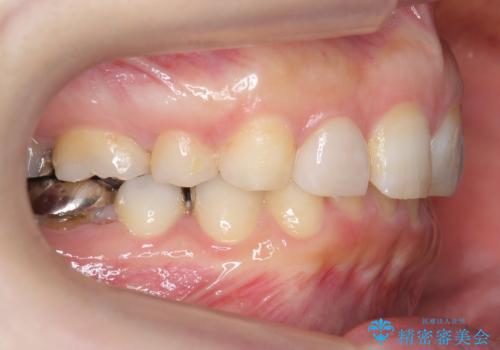

出っ歯を治したい 過蓋咬合

- 出っ歯を主訴に来院。

かみ合わせが深く、治療に時間がかかりました。

口唇の突出感がなくなり、理想的な横顔になりました。